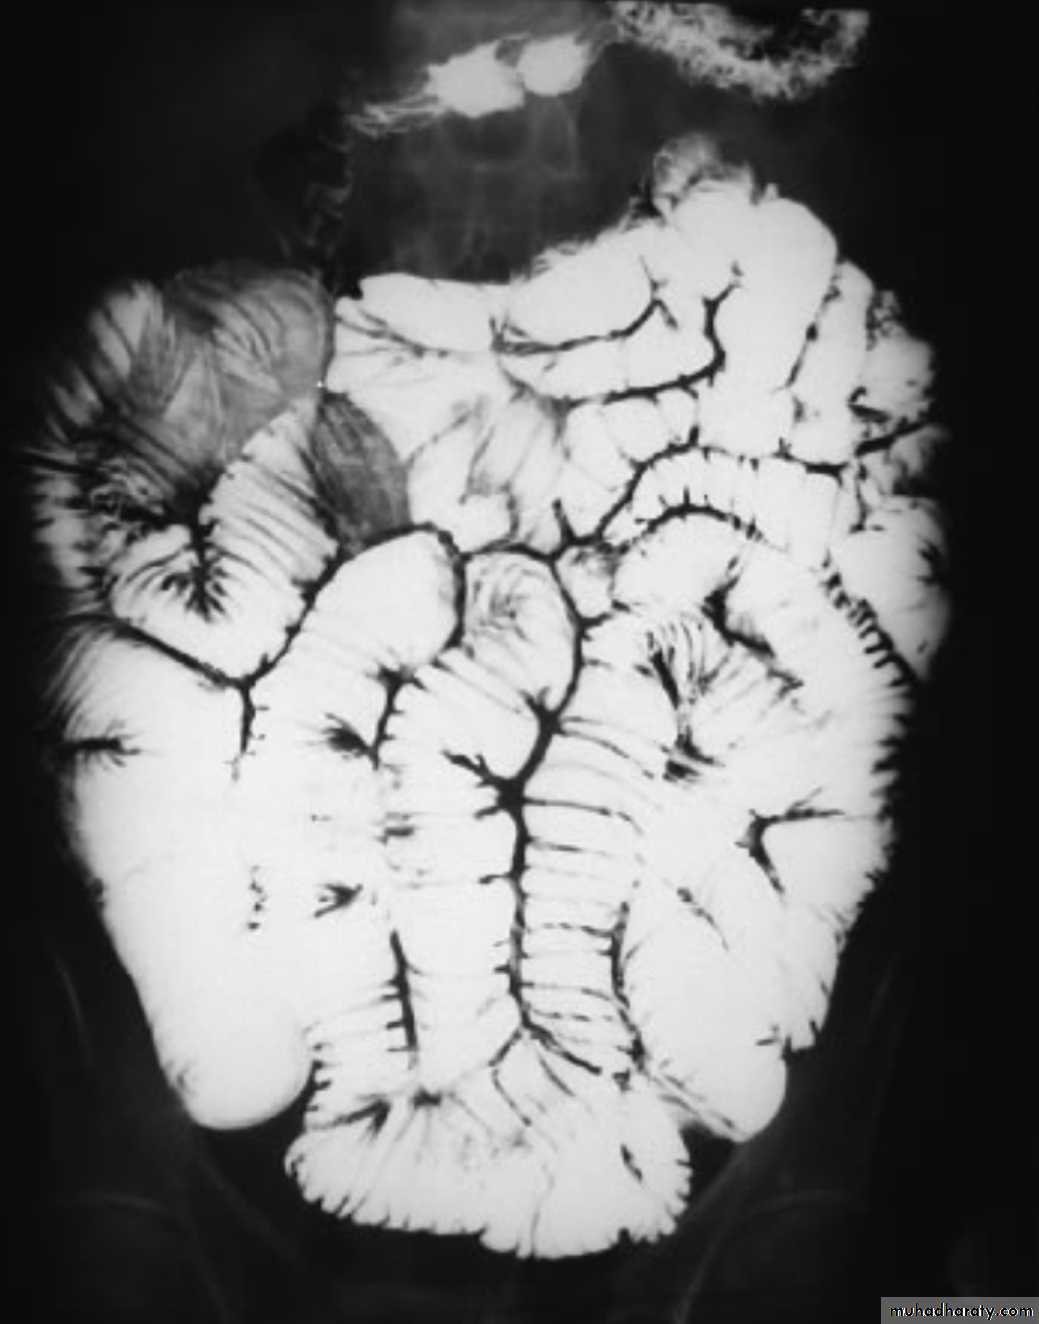

Mal absorption syndrome

Ba follow through findingsLoss of normal small bowel feathery appearance .

Dilated small bowel loops > 3.5 cm

Splaying & increase the distance between small bowel loops

Flocculation & segmentation of the Ba